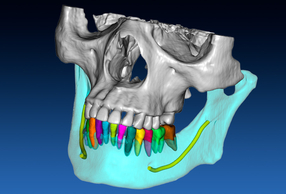

Allineare i file, tracciare la curva panoramica ed identificare i nervi mandibolari sono tutti step indispensabili per la creazione del paziente virtuale fondamentali per la buona riuscita di una chirurgia protesicamente guidata, ma richiedono tempo e un buon training per essere fatti a regola d’arte. Per non parlare delle operazioni di segmentazione di ossa, denti e corone. Il Software RealGUIDE®, a partire dalla versione 5.4, offre numerose funzioni con AI integrata grazie ai potenti algoritmi incorporati.

Con le funzioni AI integrate si passa da 3 ore di lavoro umano a soli 15 minuti di elaborazione automatica. Questi nuovi strumenti ti permettono di ottenere il tuo paziente virtuale in pochi click e con il minimo sforzo:

- tracciamento automatico della curva panoramica;

- riconoscimento assistito del nervo mandibolare;

- matching assistito DICOM/STL e STL/STL;

- segmentazione automatica dell'osso e dei singoli denti;

- estrazione automatica delle corone dai file 3D.

Allineare i file, tracciare la curva panoramica ed identificare i nervi mandibolari, sono tutti step indispensabili per la creazione del paziente virtuale, fondamentali per la buona riuscita di una chirurgia protesicamente guidata, ma richiedono tempo e un buon training per essere fatti a regola d'arte. Per non parlare delle operazioni di segmentazione di ossa, denti e corone. Dalla versione 5.4, il Software RealGUIDE™ aumenta la quantità di funzioni con AI integrata grazie ai potenti algoritmi sviluppati dal team 3Diemme. Grazie all'AI si passa da 3 ore di lavoro umano a soli 15 minuti di elaborazione automatica. Gli strumenti di intelligenza artificiale integrati ti permetteranno di ottenere il tuo paziente virtuale in pochi click e con il minimo sforzo:

- Tracciamento automatico della curva panoramica.

- Riconoscimento assistito del nervo mandibolare.

- Matching assistito DICOM/STL e STL/STL.

- Segmentazione automatica dell'osso e dei singoli denti.

- Estrazione automatica delle corone dai file 3D.